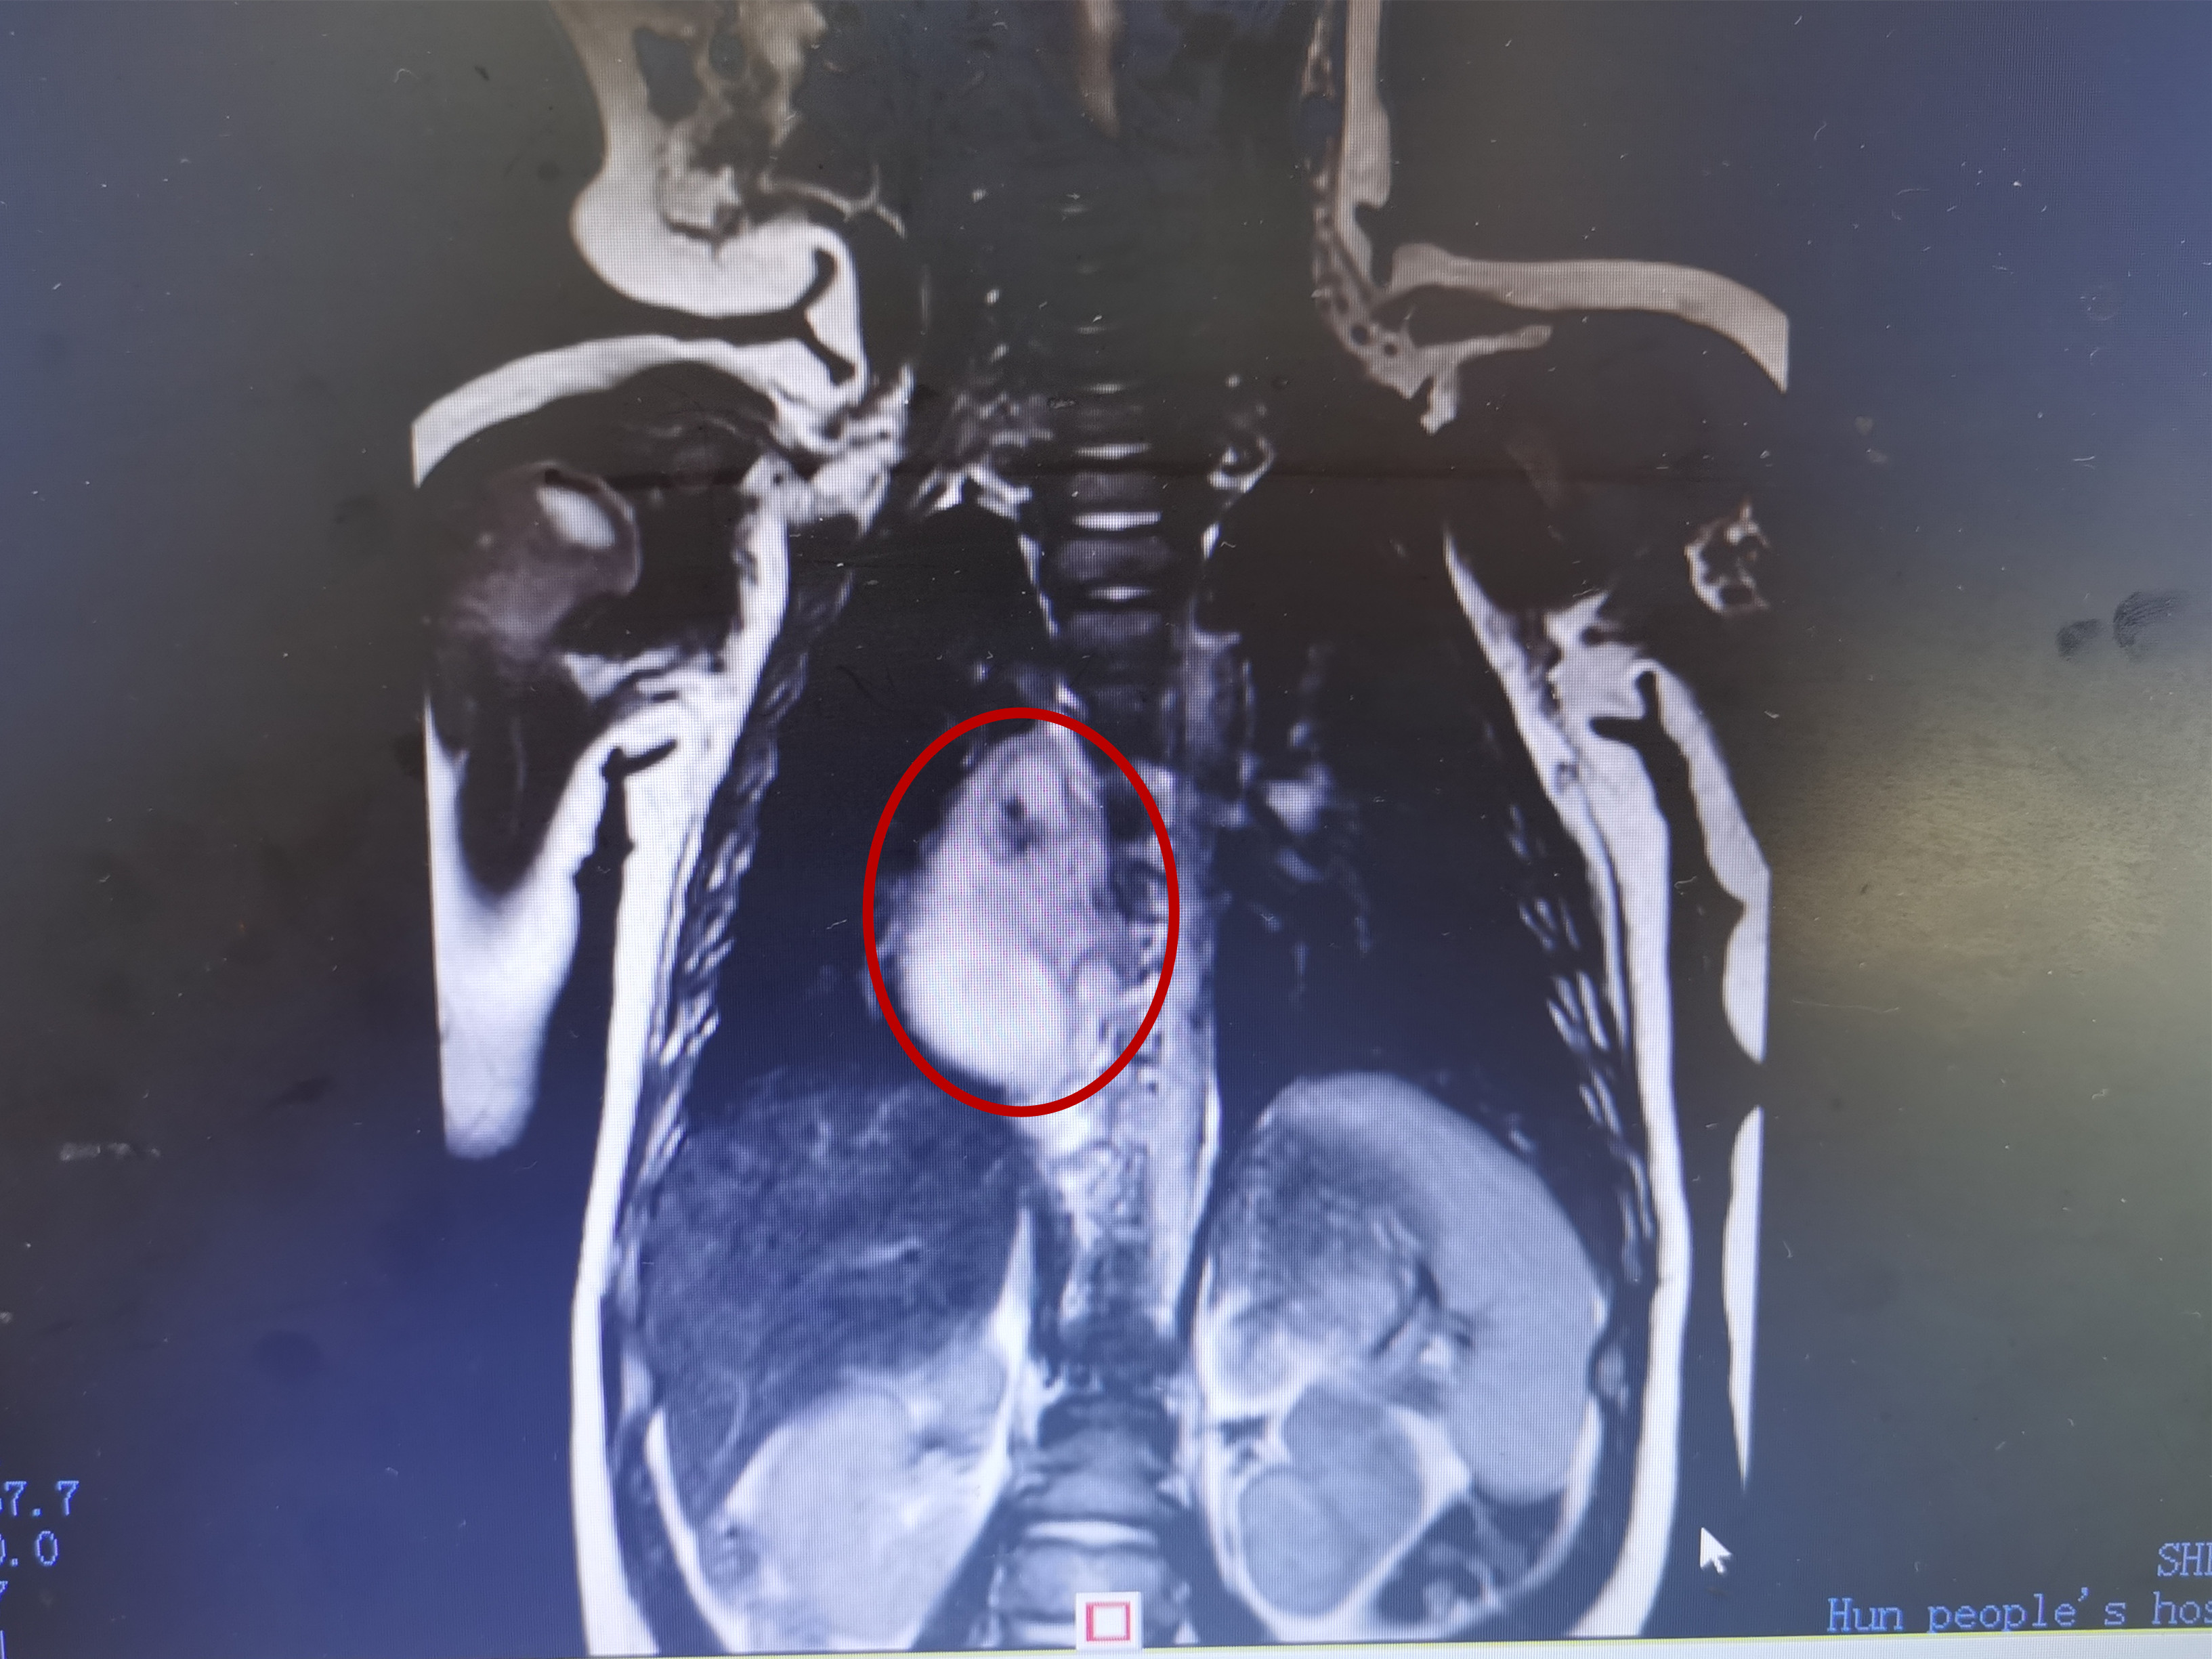

检查结果显示巨大肿瘤

希希入院后,医生发现肿瘤位于纵隔脊柱旁,有黄桃大小,经儿童血液肿瘤科、儿童外科、心胸外科等科室多学科会诊,认为应尽快确定肿块性质,通过穿刺活检,希希胸腔的肿块确诊为神经母细胞瘤,因孩子年龄小于1岁,肿瘤无远处转移和明显并发症等,可先观察并定期复查,1个月后复查肿瘤较前有所增大,再次多个学科会诊后,医生为希希制定了手术切除方案,7月20日,心胸外科和儿童外科共同为希希实施手术,手术过程中应用心脏大血管外科中的精细微操作技术,结合病理科的实时快速细胞学诊断技术,对纵膈神经母细胞瘤完整切除,并对邻近大血管、神经等重要组织进行了很好保护,手术时长2小时,出血量仅40毫升,术后希希转入PICU,经过精心细致的治疗和护理,恢复良好。